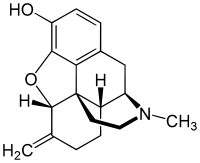

Methyldesorphine Methyldesorphine |